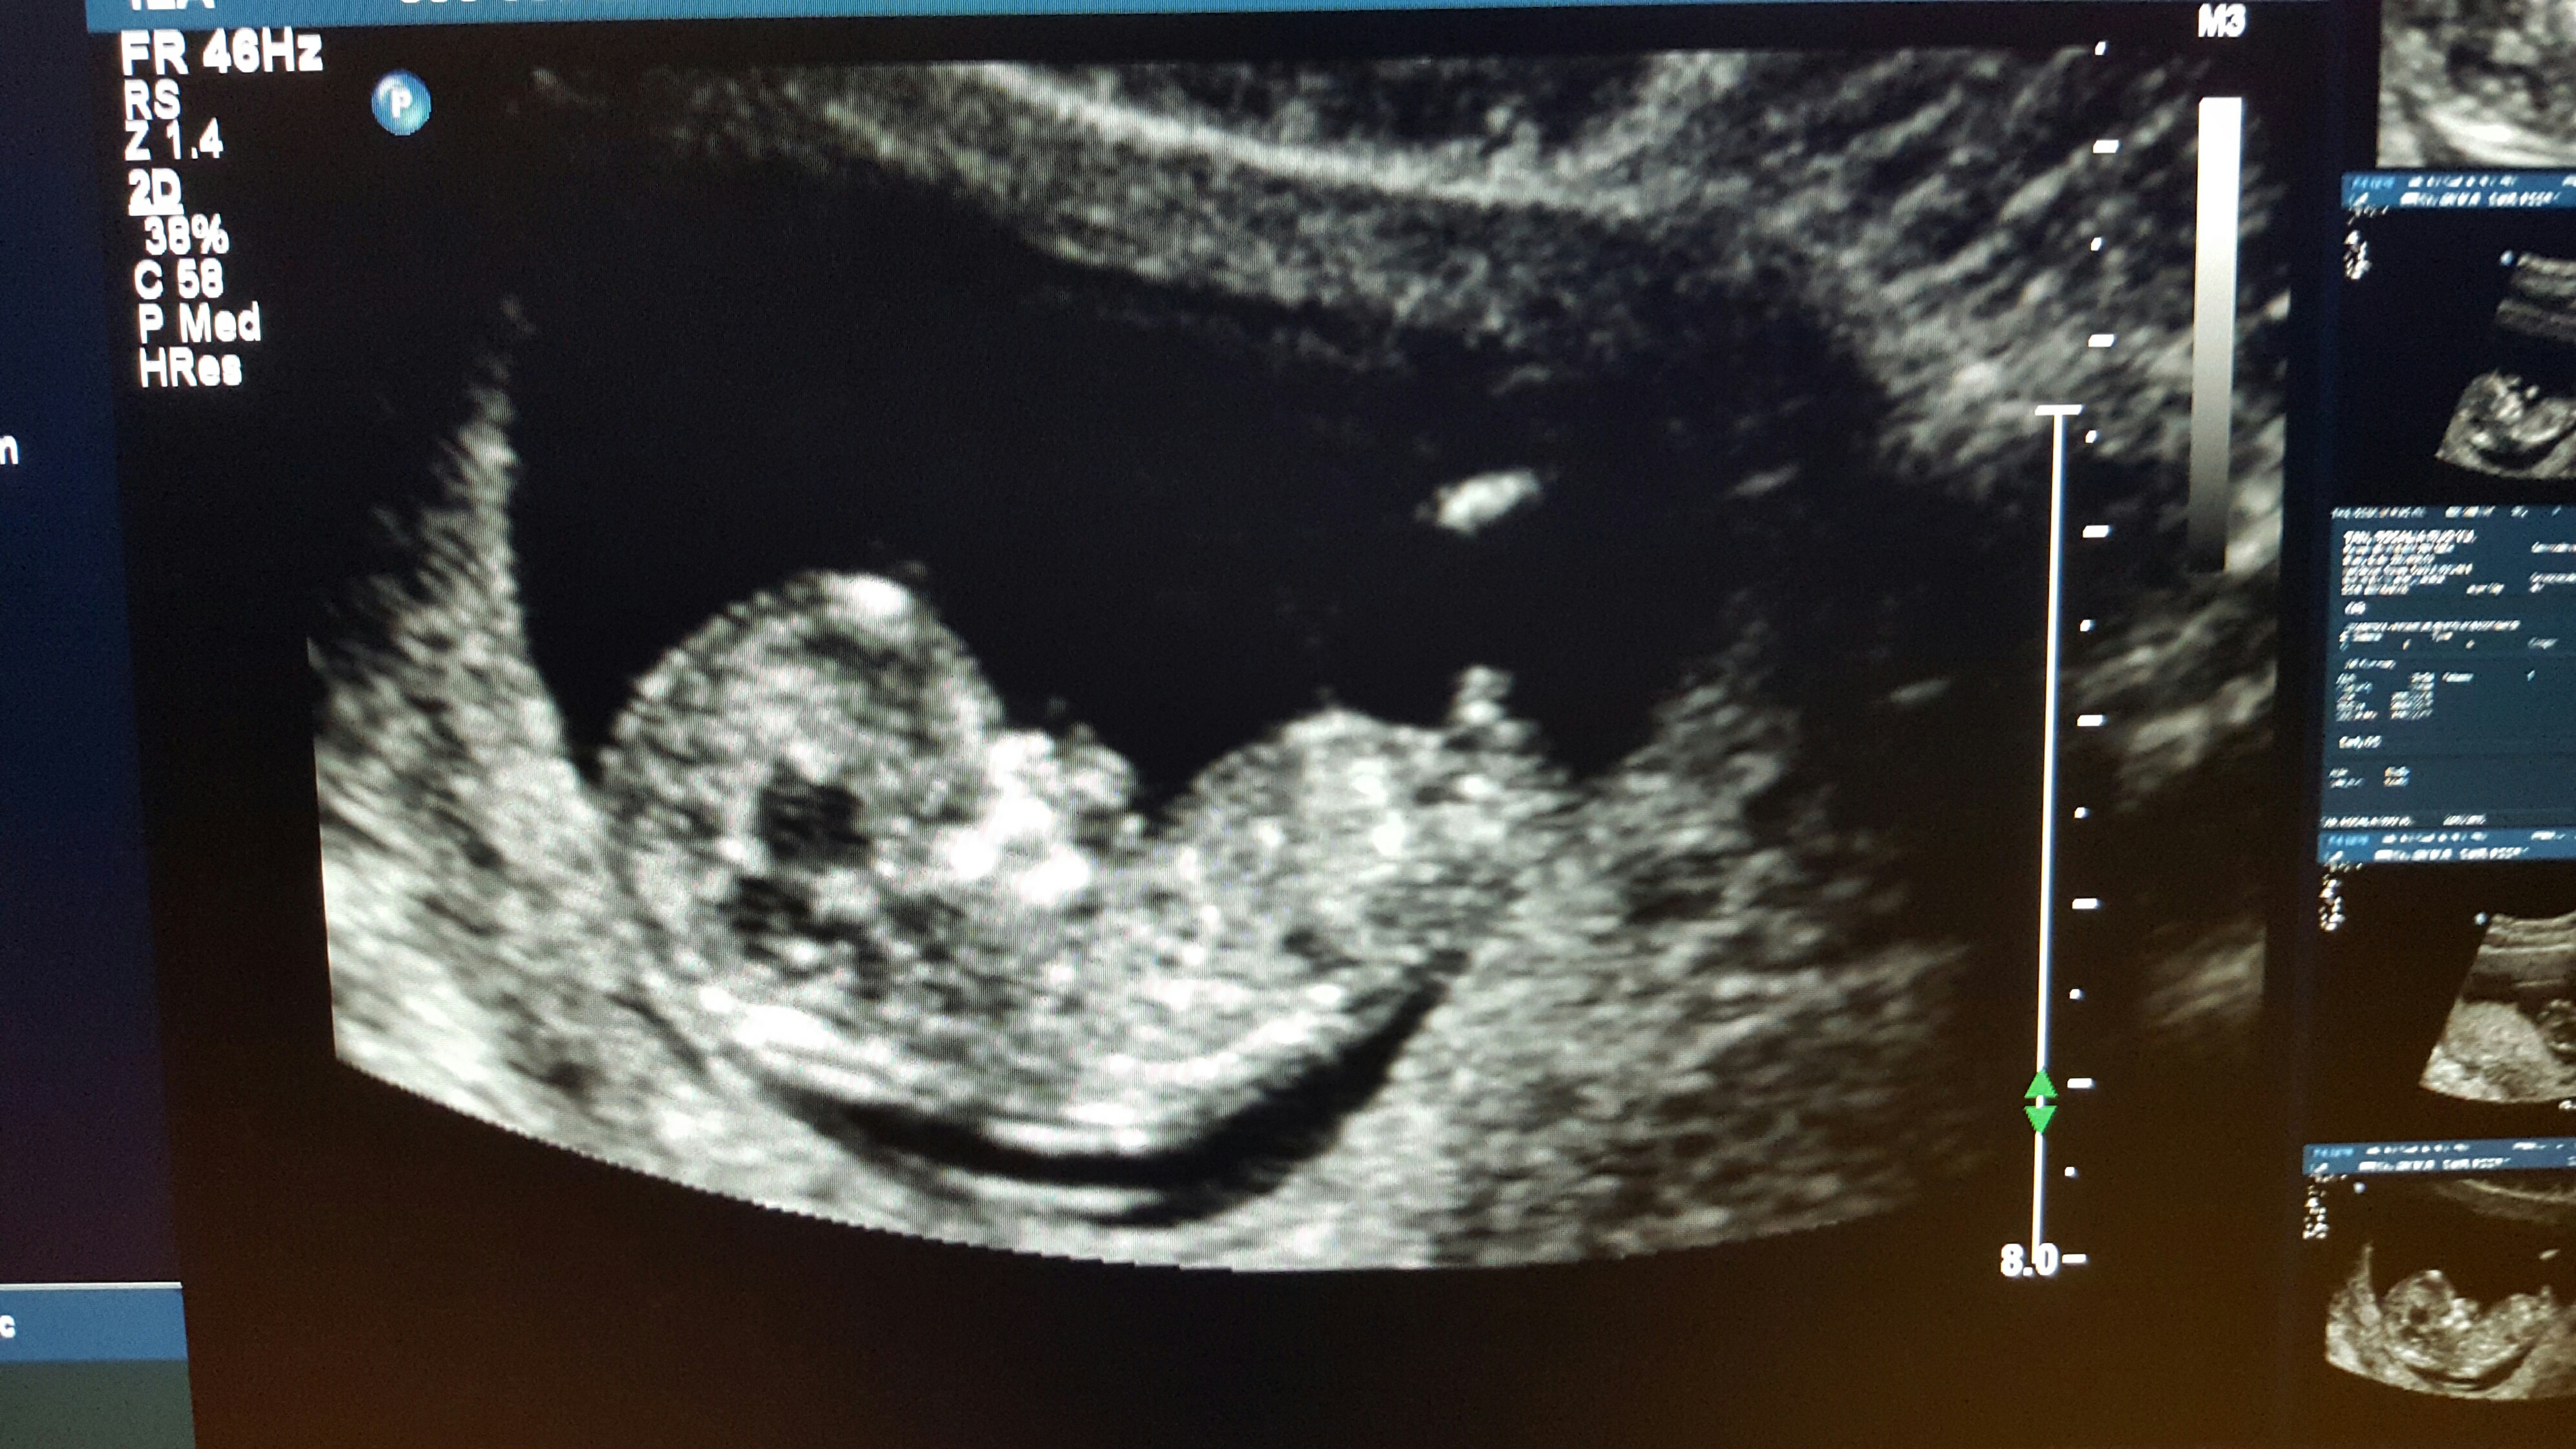

Hi everyone! Any thoughts/guesses on my 12 week ultrasound (baby measured ahead at 12+3) picture? I don't think the picture showcases the nub all that well, and I can't tell at all based on my U/S photo so I would definitely appreciate getting some predictions! Thank you all :)